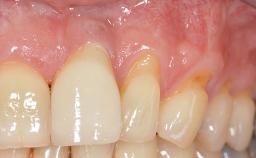

Periodontal Plastic Surgery and Prosthetic Procedures to Treat Peri-Implant Soft-Tissue Dehiscences

A 30-year-old woman was referred by her general dentist for evaluation of an esthetic complication related to previous implant treatment for congenitally missing maxillary lateral incisors. The patient’s chief complaint was the inadequate esthetic appearance of her smile. The case demonstrates the use of a combined approach to achieve optimal results. Two different flap designs - a tunnel technique and a coronally advanced flap - are employed based on the surgical objectives for the affected site.